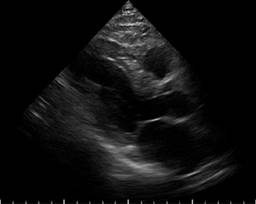

A transthoracic echocardiogram was performed that showed septoapical, apical, inferior apical akinesia, no thinned cardiac segments. Left ventricular ejection fraction (LVEF) 45%, type 1 diastolic dysfunction E/A 0.6, E/e 10, normal dimensions of the right heart chambers with normal right ventricular ejection fraction at rest. Systolic pulmonary artery pressure 26 mmHg, estimated by tricuspid reverse gradient. No pericardial effusion at rest (Figures 1 to 3). The patient evolved to be hemodynamically stable, so a stress echocardiogram was performed to search for viability/residual ischemia on the 6th day after admission to hospitalization. A 5-stage protocol was initiated, starting at 5 μg/kg/min, reaching 20 μg/kg/min. The patient persisted with septoapical and apical akinesia and developed an ischemic response due to developing basal and medial inferior hypokinesia. No changes were recorded in the electrocardiogram at this dose of dobutamine. Esmolol 30 mg intravenous single dose was administered at the beginning of the recovery phase and the study was terminated. In first minutes of recovery, the patient showed sudden deterioration in alertness and pulseless electrical activity. The echocardiogram showed pericardial effusion with a hematic appearance and echocardiographic data of tamponade (Figures 4 to 6). The patient presented cardiorespiratory arrest, so intravenous fluids were administered and an emergency pericardiocentesis was performed, achieving expansion of the right ventricle but with rapid formation of a new pericardial effusion. Later on, he presented asystole which did not revert to basic or advanced cardiovascular resuscitation.